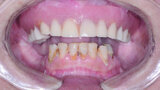

Fig 1 Vue préopératoire avec écarteur de lèvres